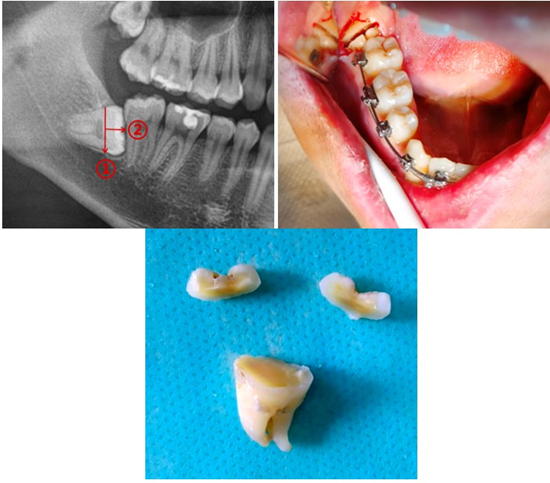

In the control group, tooth sectioning was performed in a T-shape, according to the technique described in the literature (study reference no. [12]) (Figure 2).

Figure 2: Demonstration of the T-shape technique by the author (He et al., Horizontal Third Molar Removal by T-Shaped Sectioning, J Oral Maxillofac Surg 2024).